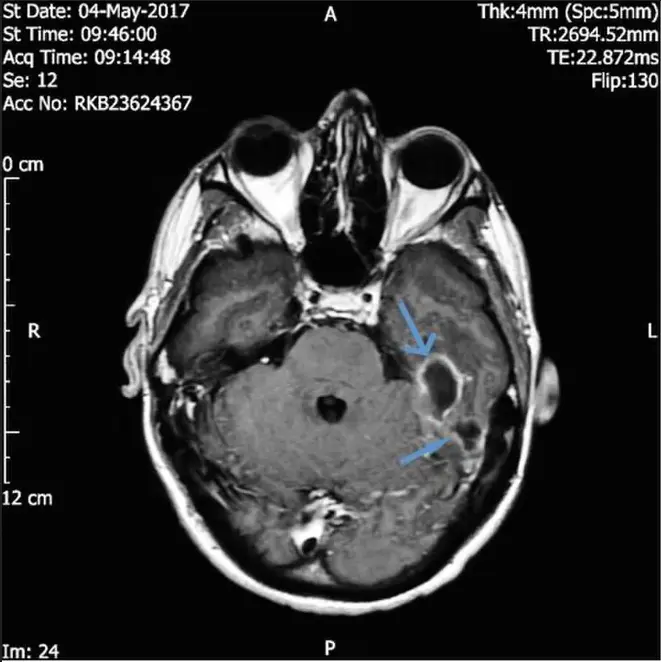

A l’hôpital, le trentenaire passe un scanner qui révèle alors la présence de deux abcès intracrâniens à proximité de son conduit auditif, responsables de ses symptômes neurologiques. Une analyse des sécrétions présentes dans son oreille gauche révèle quant à elle la présence de bactéries pathogènes du genre Pseudomonas aeruginosa. Le diagnostic peut enfin être posé avec certitude : il s’agit d’une otite externe nécrosante.